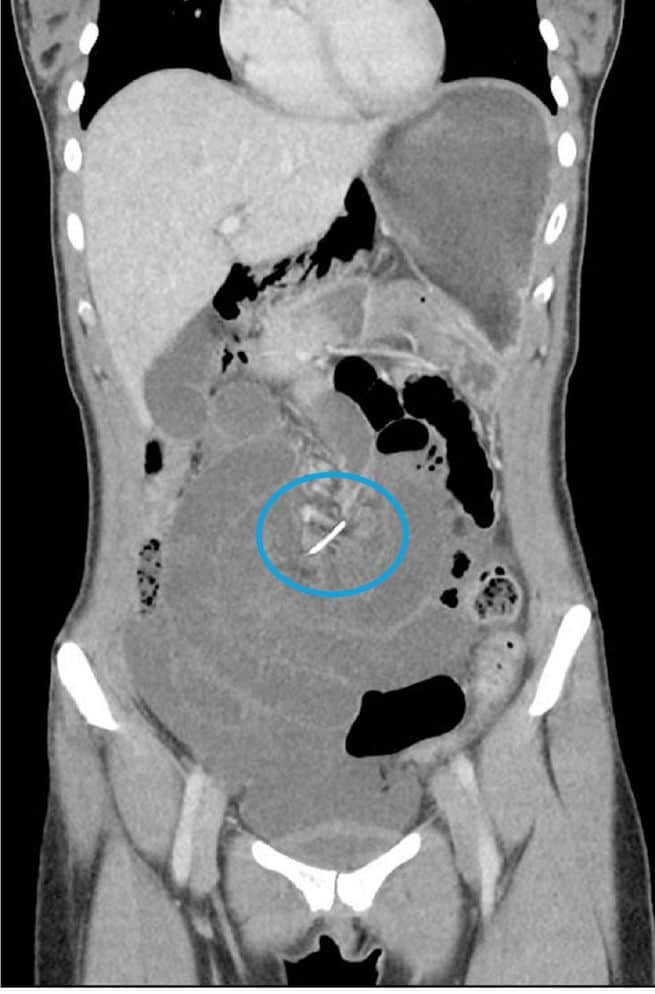

ولكن، وبعد إجراء تصوير شعاعي للسيدة بتقنية التصوير الطبقي المحوري بالأشعة السنية، أظهرت النتائج بأن ثمّة جسم غريب يوجد خلف سرّة البطن تقريباً، وكان الجسم عبارة عن سلك معدني يخز أمعاء السيدة.

تقول شيبرد: "لقد أُصبنا جميعاً بالدهشة، فلم نكن نتوقع ذلك أبداً. فقد اشتبهنا في البداية بأن يكون ذلك الجسم عبارة عن عظمة سمكة، لأن الناس كثيراً ما يبتلعونها عن غير قصد فتعلق في أحد أجزاء الجهاز الهضمي، إلا أن الكثافة الكبيرة للجسم الذي ظهرت صورته في اختبارات الطبقي المحوري كانت تشير إلى أنه جسم معدني."

وبحسب الأطباء، فإن المريضة كانت تستخدم جهازاً لتقويم الأسنان منذ ما يقرب من عشر سنوات، وقد ابتلعت فيما يبدو أحد أسلاك الجهاز المستخدم لرصف الأسنان. وقد بلغ ذلك السلك من الطول حوالي 7 سنتيمترات.